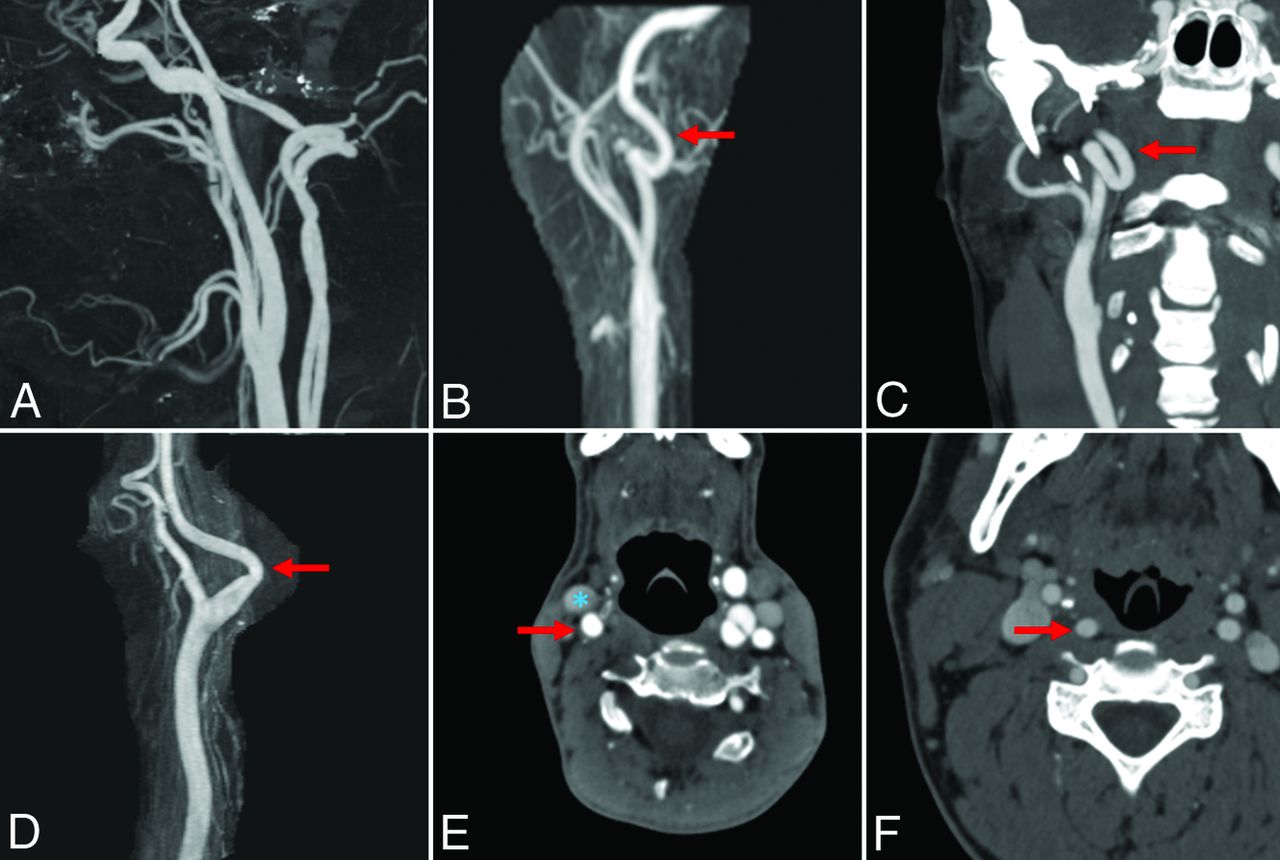

Radiologists blinded to each patient's medical history reviewed the CTA or MRA imaging to evaluate the presence of tortuosity within the cervical segment of the internal carotid artery per previously described methods.2 Radiologists had access to multiplanar reformatted images and 3D reconstructions as available. Carotid artery tortuosity was defined as the presence of shape deformations including coils, loops, and kinks. Specifically, shape deformations were assessed using the following criteria: 1) The presence of loops was defined by findings of C- or S-shaped deformities wherein the vessel exhibited 2 turns with angles of ≤90°; 2) coils exhibited complete, 360°, turns in the vessel; and 3) kinks were observed as singular ≥90° bends in the vessel. Furthermore, we ex-plored path alterations including retrojugular and retropharyngeal anatomy. Path alterations were defined by the following criteria: 1) A retrojugular carotid path was defined as >50% of the internal carotid artery by cross-sectional area traveling posterior to the internal jugular vein; and 2) a retropharyngeal path was defined as >50% of the ICA traveling behind (medially to) the lateral edge of the pharynx. Examples of tortuosity and path alterations can be found in the Figure. Additionally, the presence of atherosclerotic changes and fibromuscular dysplasia was assessed.

Examples of carotid artery tortuosity and path alterations. A, Sagittal CTA reconstruction shows normal bilateral carotid and vertebral arteries. B, Anterior reconstruction MRA of a patient with Marfan syndrome shows a carotid loop (red arrow). C, Coronal MIP CTA of a patient with Marfan syndrome shows bilateral carotid coils (red arrow). D, Sagittal–reconstruction MRA of a patient with EDS shows a carotid artery (red arrow) kink. E, Axial CTA of a patient with LDS shows a retrojugular carotid artery (carotid artery, red arrow; jugular vein, blue asterisk). F, Axial CTA of a patient with Marfan syndrome demonstrates a retropharyngeal carotid artery (red arrow) course.